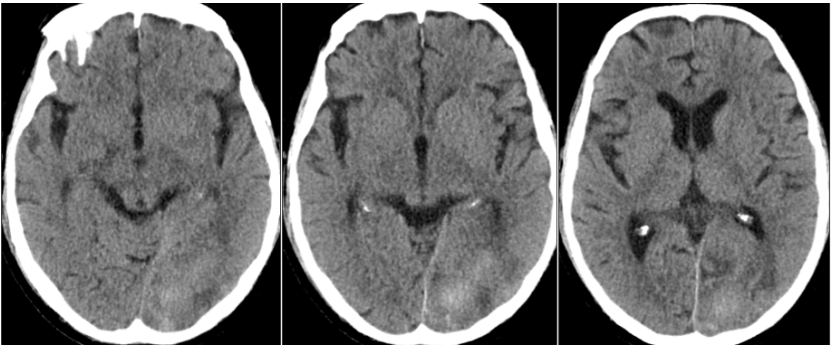

2023年2月11日头部CT显示病灶较2月3日有所吸收(图10),胸部CT示双肺磨玻璃影和实变影较前减少(图11)

图片

图10  头部CT(2023-02-11)

图11  胸部CT(2023-02-11)